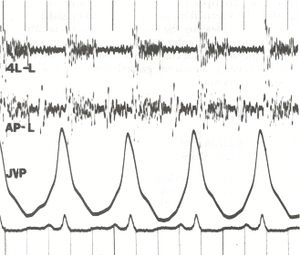

폐고혈압의 다른 전형적인 징후로는 제2심음의 폐 구성 요소 강조, 우심실 제3심음, 흉골 연접 융기(우심실 비대를 나타냄)가 있다. 우심 부전으로 인한 전신 울혈의 징후로는 경정맥압 상승, 복수, 간-경정맥 반사가 있다.[12][13][16] 삼첨판 폐쇄 부전 및 폐동맥판 역류 유무도 확인하며, 이는 폐고혈압과 관련이 있을 수 있다.[12][13][17]